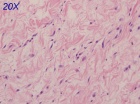

83 year old male with a two month history of a right thigh mass

Zoom image: Cell stain Cell stain.